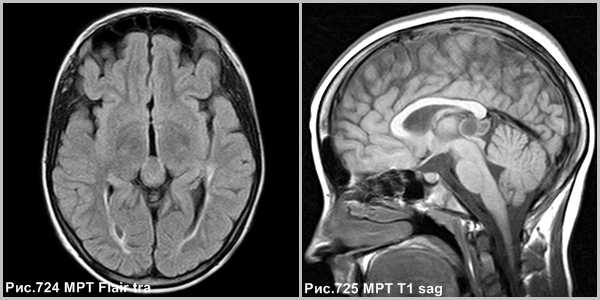

Пинеоцитома - доброкачественная опухоль, возникающая из ткани шишковидной железы, имеющая четкие контуры (рис.724, 725).

Морфология и биологическое поведение

Пинеоцитома - доброкачественная опухоль, происходящая из паренхимы corpus pineale, хорошо ограниченное, инкапсулированное, медленно растущее, неинвазивное поражение. Опухоль может содержать кальцинаты по периферии [137]. Размеры образования могут быть различны, но это не связано с атипией опухоли. На КТ пинеоцитомы были описаны как → или слегка ↑, на МРТ это солидная фракция описывается, как ↓T1 и →Т2 [137].

Объёмное образование шишковидной железы, представленное мягкотканным образованием с наличием капсулы (стрелки на рис.729, 730). Пинеоцитома может иметь кисты (головка стрелки на рис.728).